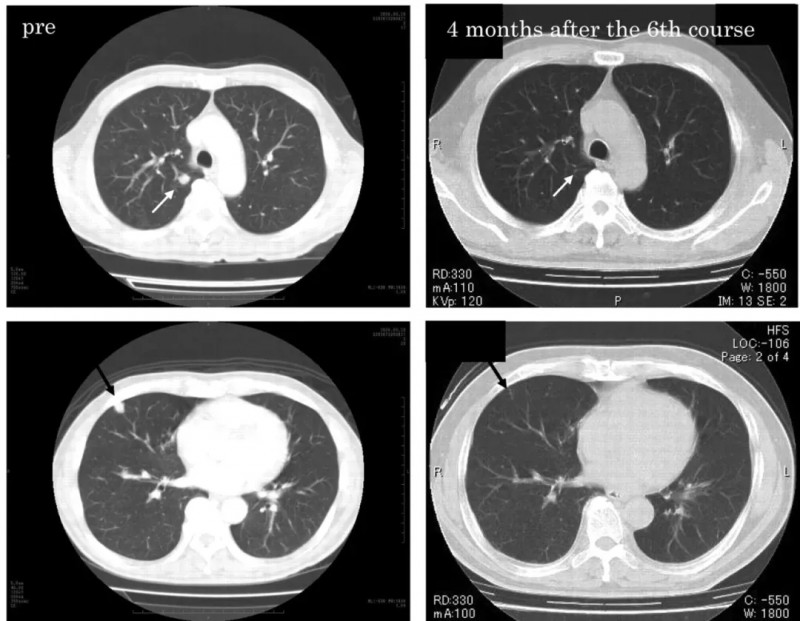

《Anticancer Research》曾报道一则经典案例:一位61岁男性患者确诊位右侧透明细胞型肾细胞癌(3级,pT1b期)伴肺转移,行根治性肾切除术后接受3个月干扰素α(IFN-α)治疗,CT显示肿瘤负荷无明显变化。

治疗转折出现在IFN-α洗脱期1个月后:患者通过白细胞分离术获取外周血单核细胞(PBMC),静脉注射IL-2与唑来膦酸,随后输注活化的Vγ2Vδ2T细胞。

疗效令人振奋:患者多发性肺转移灶在回输Vγ2Vδ2 T细胞3个疗程后显著缓解,6个疗程后完全消失;完成最后一个疗程后,患者持续2年保持完全缓解(CR)状态(详见下图),且未接受额外针对肾癌的治疗。

▲图源“anticancer research”,版权归原作者所有,如无意中侵犯了知识产权,请联系我们删除